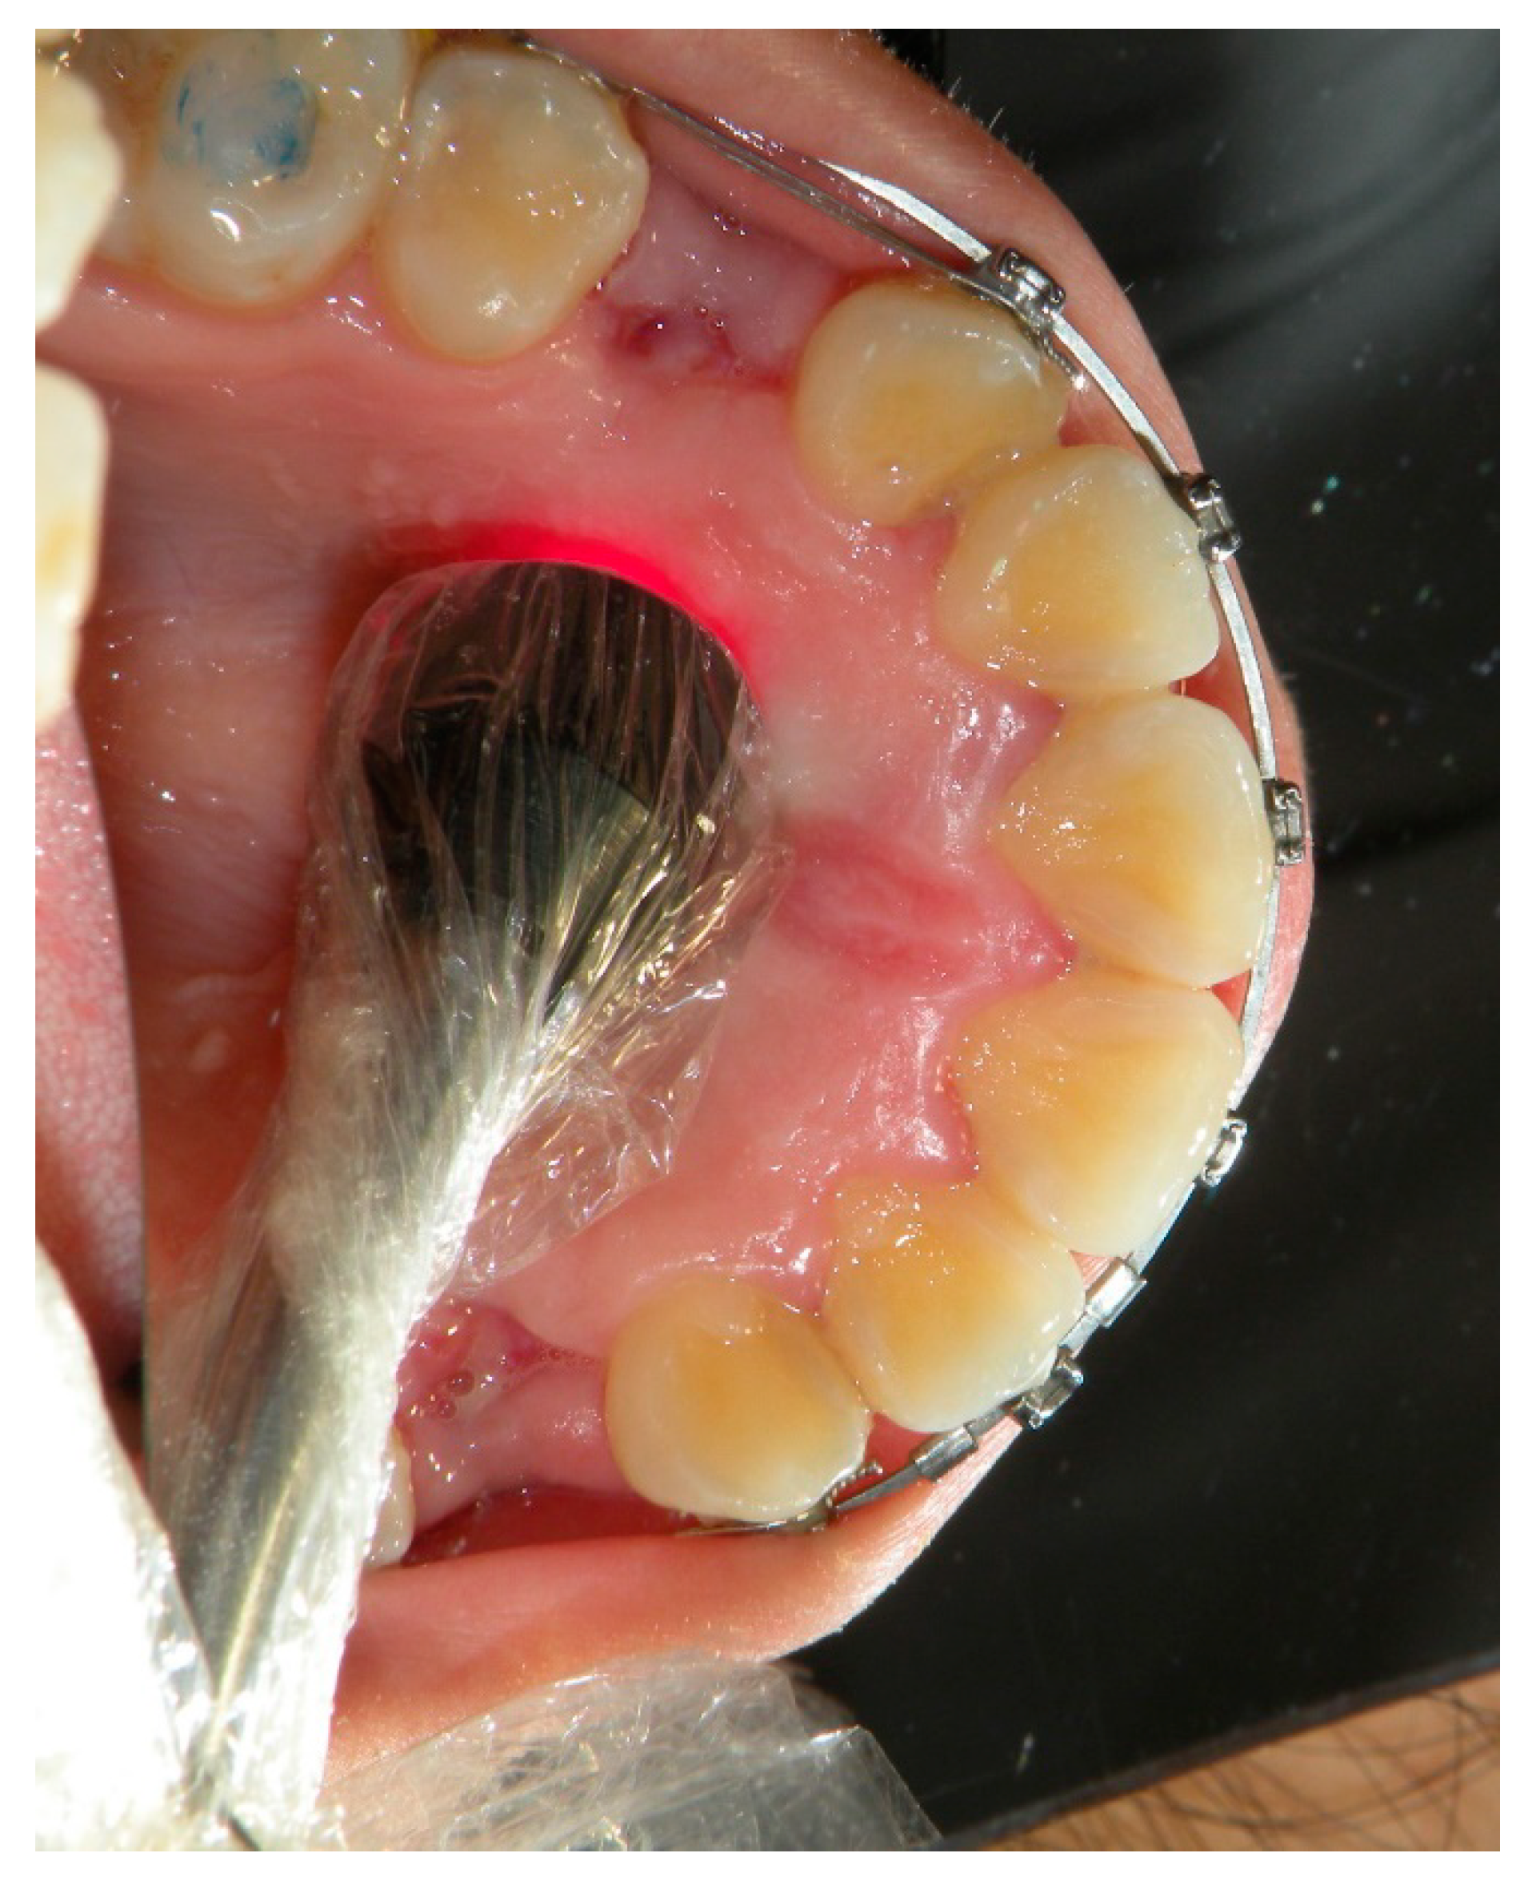

Figure 2.

Palatal view of the third apical irradiation of the same canine in Figure 1.

The areas chosen for the irradiation of the canine were the vestibular (Figure 1) and palatal (Figure 2) aspects of the periodontal ligament for a total of six points for the laser application: three palatal and three vestibular points at the apical, middle, and cervical third level of the canine root (Table 1).